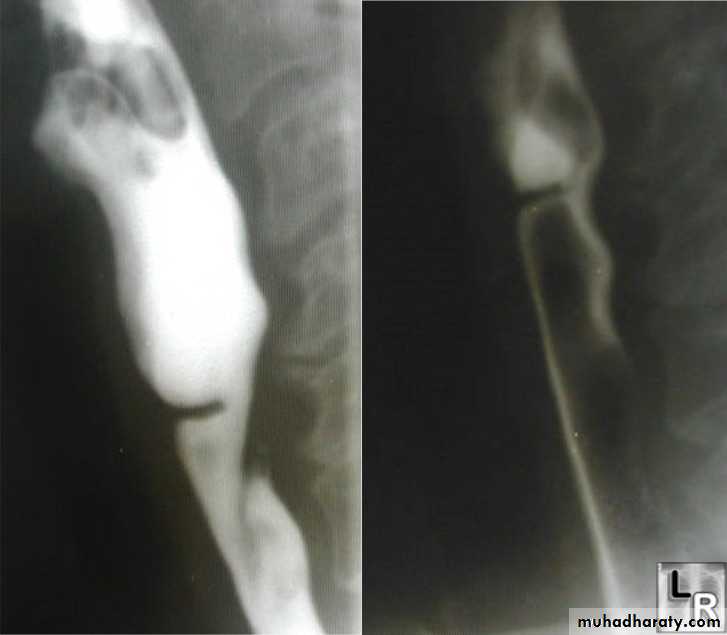

• 3- In cervical portion at level of C5

• 4- Posteriorly (Killience dehiscent)

• 5- Lateral view show increased pre-vertebral space with air fluid level.

• 6- Confirmed by Ba. Swallow.

2-In the middle third at level of hilum

3- Up ward direction of diverticulum

4- Irregular base